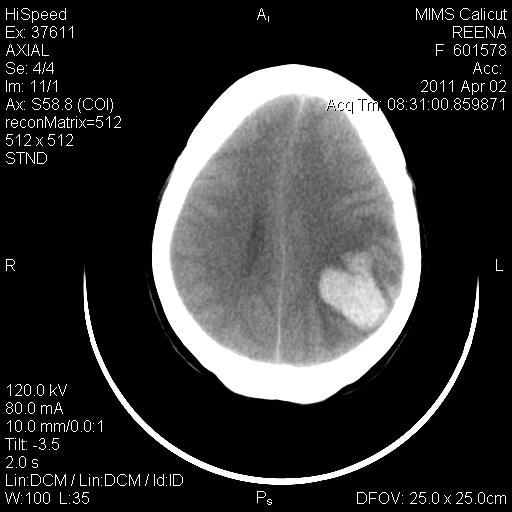

IMAGING-CT BRAIN

Left tempero parietal haematoma 4.1 cm x 3.5 cm with mass effect and midline shift of about 9 mm